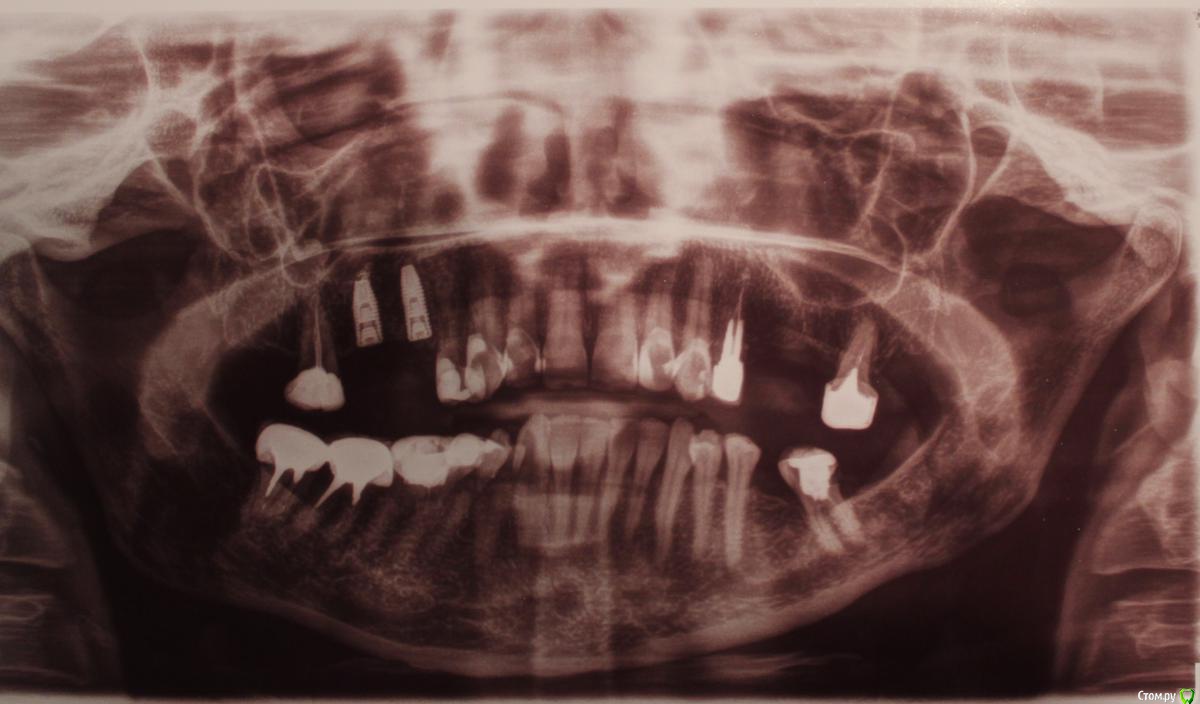

Patient_Nobel Опубликовано 18 мая, 2019 Поделиться Опубликовано 18 мая, 2019 Здравствуйте, форумчане!Были установлены два импланта Nobel. После операции сделали панорамный снимок. Дома посмотрела и расстроилась - один из имплантов установлен очень близко к зубу.Как я вижу, то нет места для установления коронки.Что это? Ошибка хирурга? или что-то можно сделать в такой ситуации? Ведь имплант уже не переставить(((( Ссылка на комментарий

kramer Опубликовано 18 мая, 2019 Поделиться Опубликовано 18 мая, 2019 Нормально там всё 1 Ссылка на комментарий

Большой Зеленый Опубликовано 18 мая, 2019 Поделиться Опубликовано 18 мая, 2019 Все отлично! Просто небольшое искажение .Это просто такой снимок ) Спите спокойно 1 Ссылка на комментарий